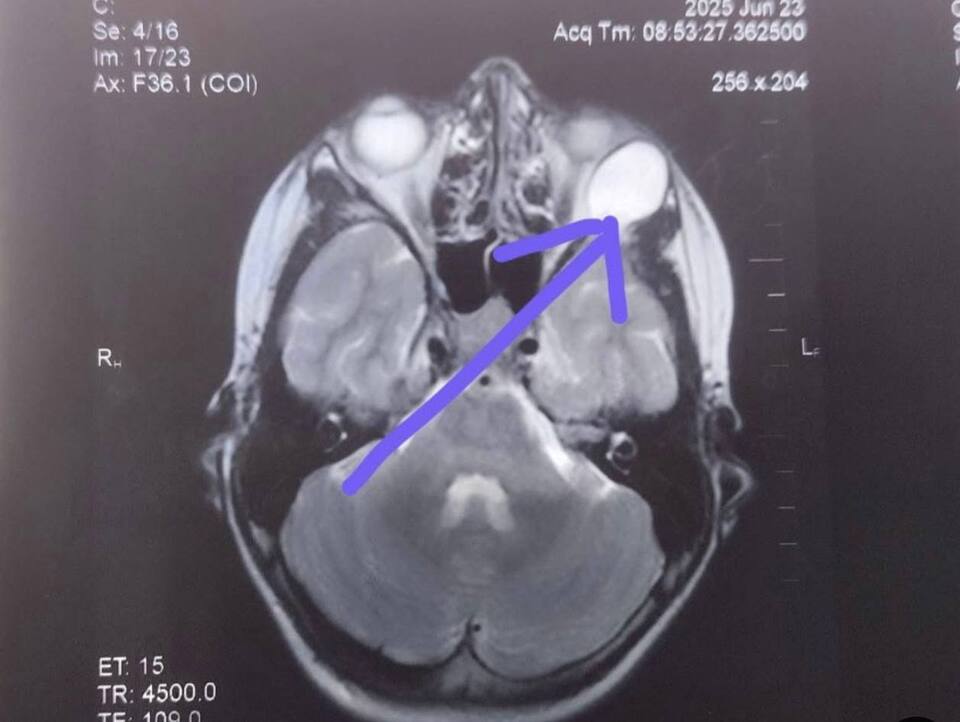

Після проведення МРТ обстеження виявили новоутвір великих розмірів (приблизно 20 мм), який зміщував очне яблуко та викликав у дитини наявні симптоми.